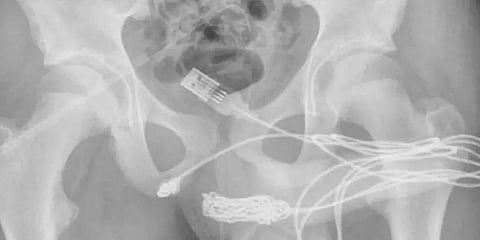

இதனையடுத்து, USB கேபிளின் இருபுற போர்ட்களும் சிறுவனின் சிறுநீர்க்குழாய் பகுதியில் நீண்டுக் கொண்டு இருப்பது கண்டறியப்பட்டது. அதே சமயத்தில் முடிச்சு போடப்பட்ட கம்பியின் நடுப்பகுதியில் சிறுநீர்க்குழாய்க்குள் இருந்திருக்கிறது. ஏகப்பட்ட முடிச்சுகள் இருந்ததால் உலோக கம்பியை கொண்டு கேபிளை அகற்றுவது கடினமான வேலையாக இருந்ததால் அறுவை சிகிச்சை செய்ய வேண்டிய கட்டாயம் ஏற்பட்டது.

ஆகவே உள்ளே சிக்கியிருக்கும் கேபிளை அணுக வடிகுழாய்கள் பொருத்தப்பட்டு பிறப்புறுப்புக்கும், ஆசனவாய்க்கும் இடையே செருகி, வெளிப்புற சிறுநீர்க்குழாய் வழியாக வெற்றிகரமாக வெளியே இழுக்கப்பட்டது. இதனையடுத்து மருத்துவர்களின் கண்காணிப்பில் வைக்கப்பட்டிருந்த சிறுவன் டிஸ்சார்ஜ் செய்யப்பட்டார். 15 நாட்களுக்கு பிறகு பொருத்தப்பட்ட வடிகுழாயும் அகற்றப்பட்டு இருக்கிறது.” என ஆய்வறிக்கையில் குறிப்பிடப்பட்டிருக்கிறது.